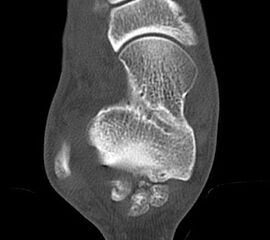

Reseziertes Os trigonum sowie prä- und postoperatives seitliches Röntgenbild nach arthroskopischer Entfernung eines Os trigonum.

Abbildung Nr. 19-22

Knochenresektat sowie präoperatives CT (Sagittal- und Transversalebene) und intraoperative Bildwandlerkontrolle im seitlichen Strahlengang nach arthroskopischer Entfernung multipler Ossikel am dorsalen OSG/USG.

Große osteophytäre Anbauten, welche die FHL-Sehne vollständig ummauern, sind ebenfalls sehr gut in der beschriebenen Technik adressierbar. Präoperatives CT und intraoperative Bildwandlerkontrolle im seitlichen Strahlengang (linke Seite).